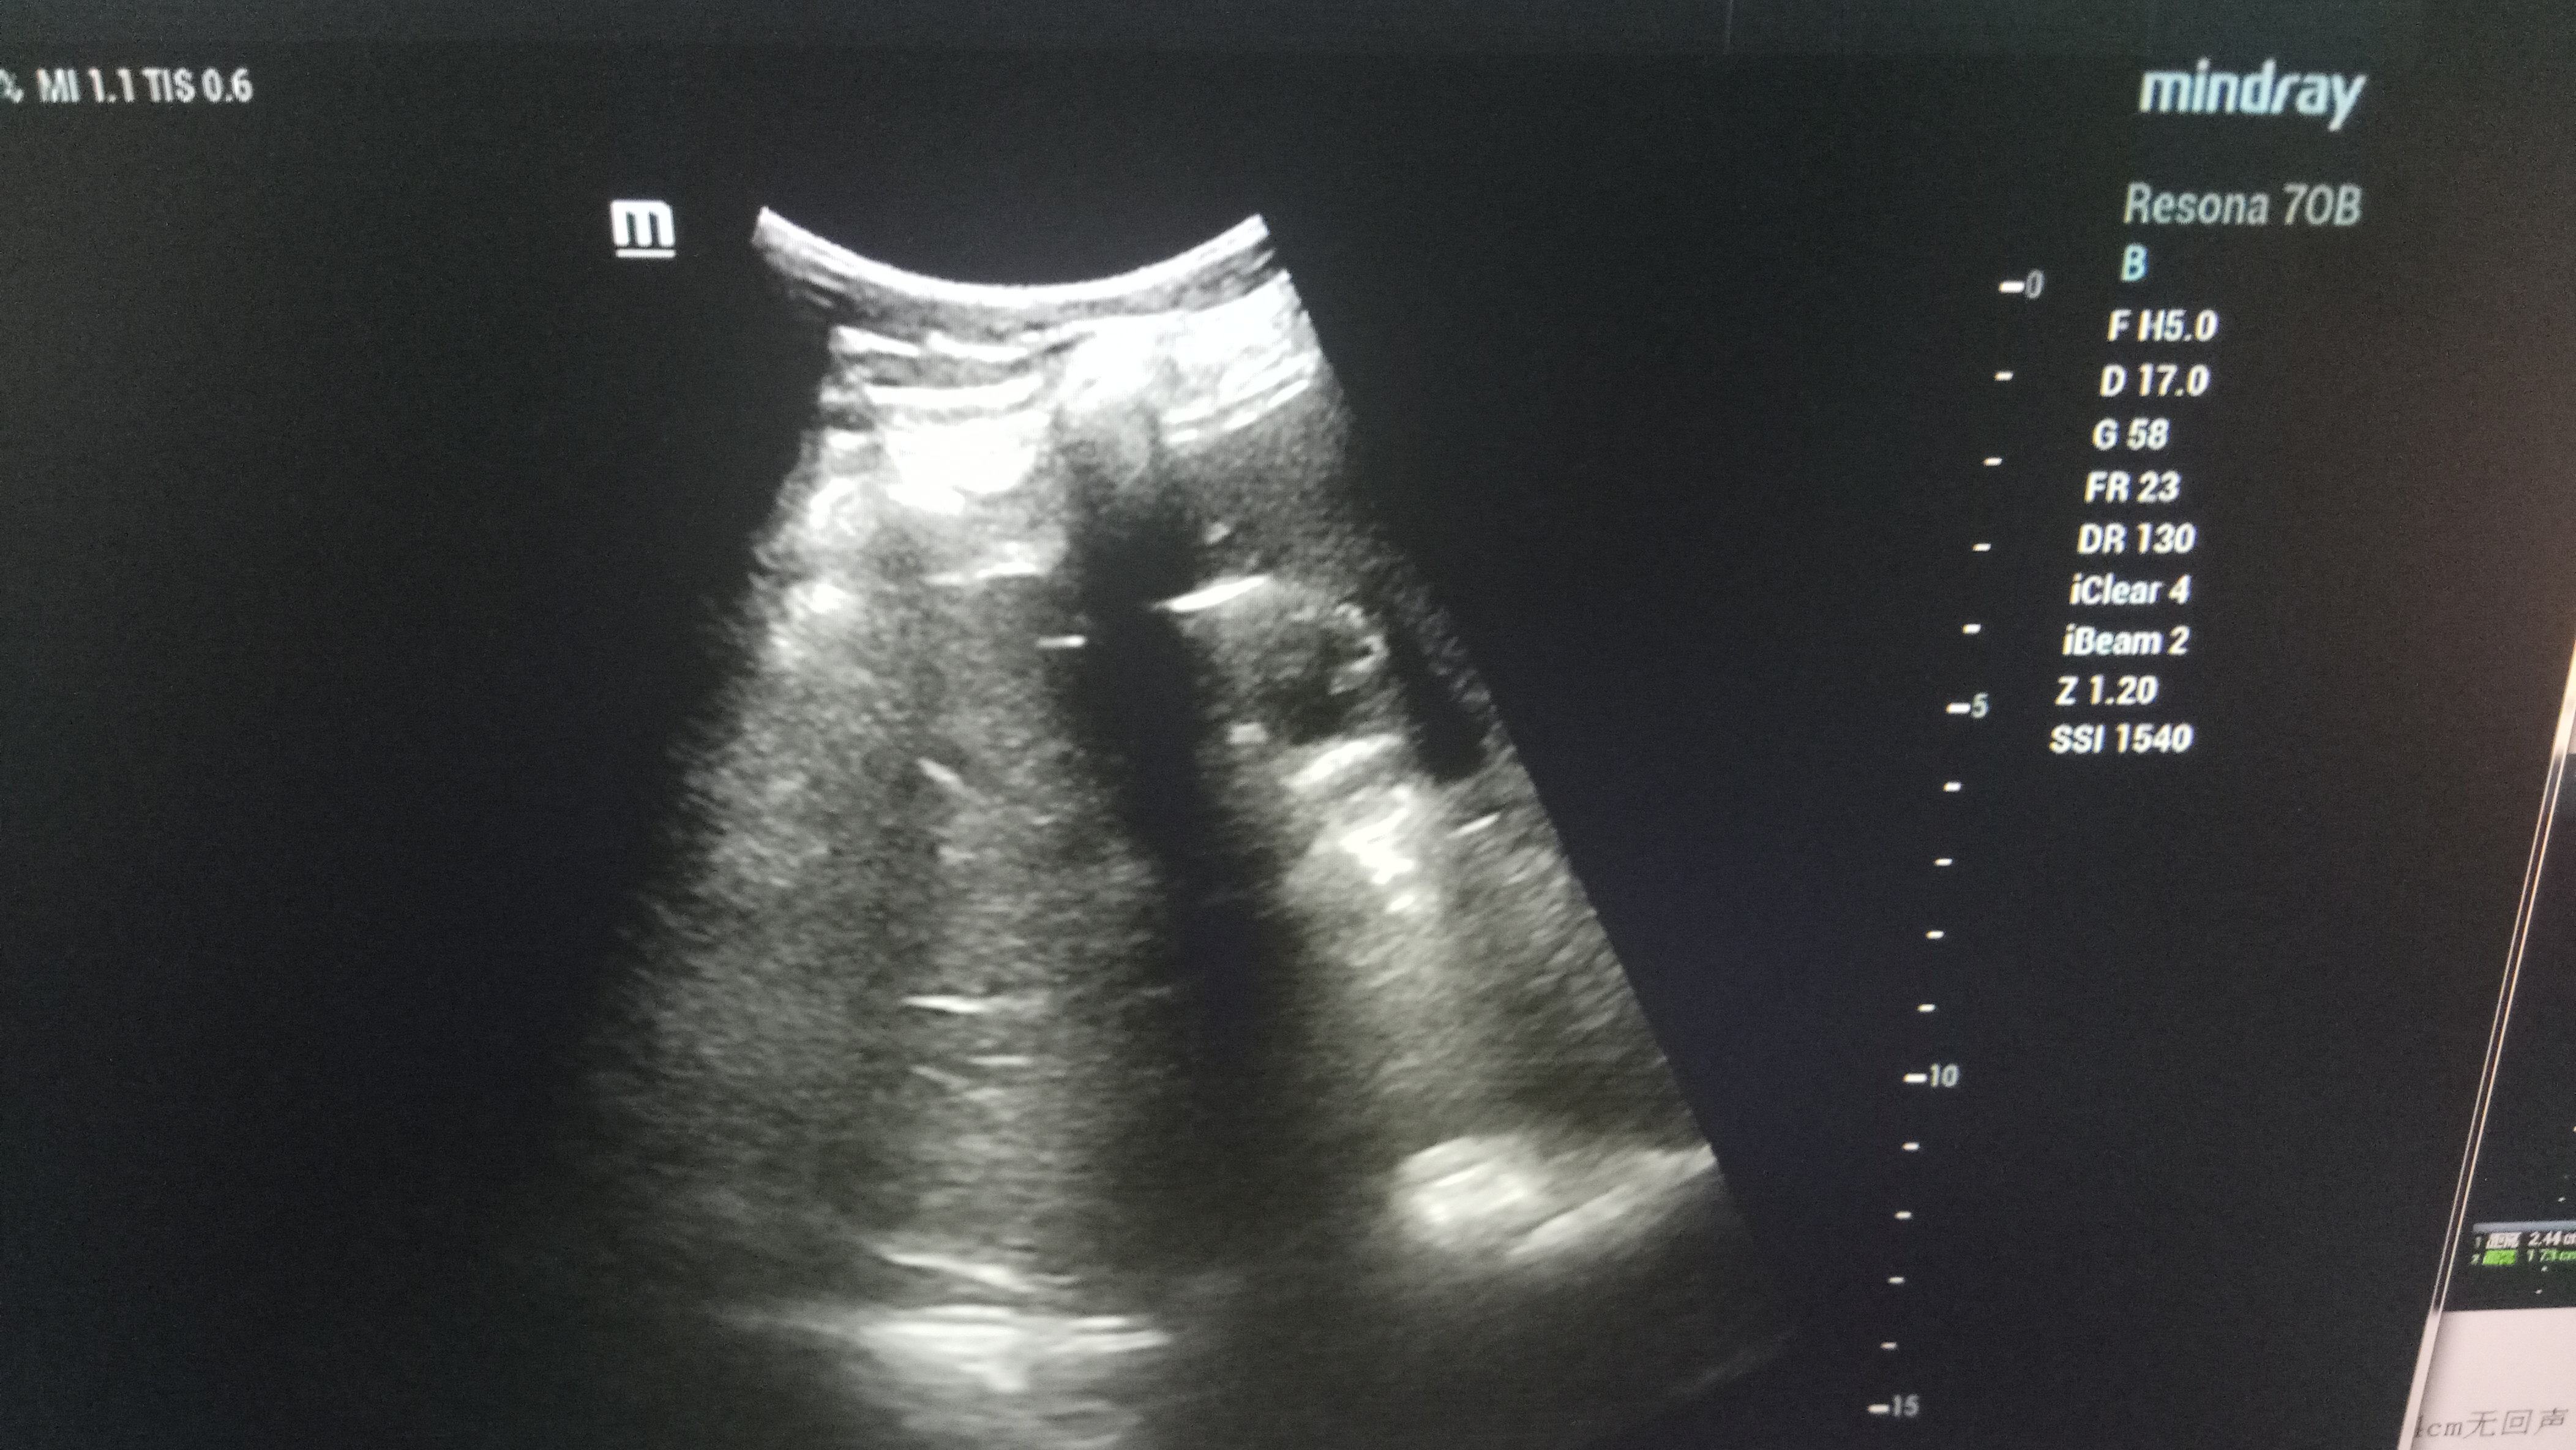

近日,21点游戏攻略站 超声科在高陵区医院成功开展了一例超声引导下肝囊肿抽吸硬化治疗术。患者前段时间查出肝囊肿,因开腹手术风险性大且痛苦,遂联系了高陵区医院超声科,在21点游戏攻略站 超声科主任展小军与对口支援医生杨艳秋的紧密配合下,短短30分钟,通过一根穿刺针,直径近7cm的肝囊肿就被完全抽吸硬化完毕,患者生命体征平稳,休息几小时后已活动自如。

超声介入微创诊疗技术是在实时超声的监视和引导下,完成各种穿刺、活检以及抽吸、插管、注药治疗等操作,达到与外科手术相当的效果,具有创伤小、恢复快、无辐射、介入治疗定位精确等优点。可治疗全身各部位囊肿,尤其是巧克力囊肿效果更佳,还有全身各部位肿瘤的活检和治疗,超声引导下微创治疗是未来医学发展方向。